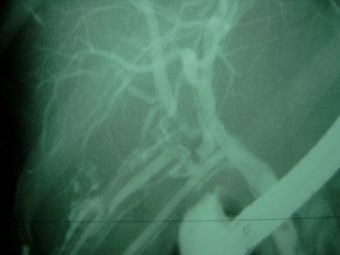

Lesión de conducto hepático derecho post colecistectomía

Envíado por Dr. Carlos Miguel Zavaleta Consuegra